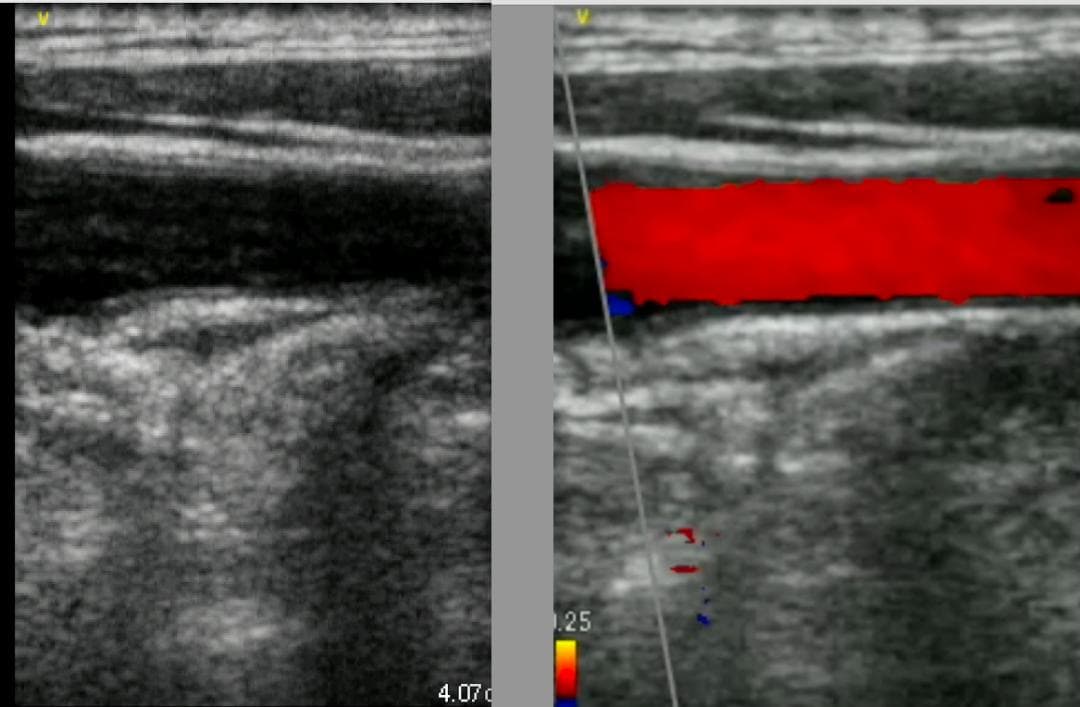

おわかりになる方のみの購入をお願いいたします実際に実施した写真をあげました正常肝臓、胆石症、頸動脈プラーク、同じく頸動脈プラーク、Mrの収縮期、同じくM弁の開放期とA弁の開放期、腹部大動脈瘤、正常の頸動脈、甲状腺右葉の結節、前立腺肥大画像の描出は条件によりますがご検討をお願いいたします経年変化、使用に伴うスレや傷などがあります機能に問題はありませんスキャンは心血管、腹部、体表に対応します外部接続端子のカバーが一部壊れていますが蓋は閉まりますバッテリーはフル充電されますが劣化はあると思います医療用モニタリング機器 Vscan Extend、GE- モデル名: Vscan Extend- ブランド: GE- 色: ホワイト- 機能: 医療用モニタリング機器ご覧いただきありがとうございます。。[新品未使用品]KT TAPE ブラック 25cm プレカット 150枚入